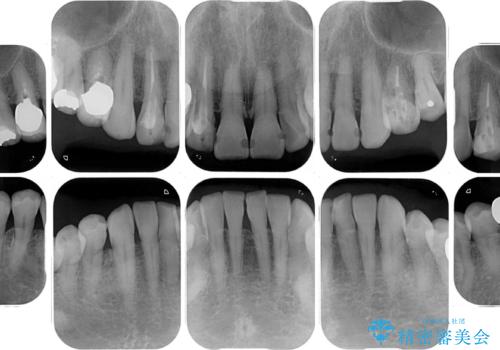

診察したところ、前歯は反対咬合であり、その影響で抜歯が必要な奥歯があることが分かりました。

抜歯が必要な奥歯は、インプラント並びにブリッジにより補綴を行い、上下前歯は反対咬合を改善させるように補綴治療を行うこととしました。

健全な歯を削ってセラミッククラウンに置き換えることは、本来避けるべき治療と考えますが、今回は①患者様が60歳を越えていること、②要改善の咬合により抜歯が必要な奥歯があること、③反対咬合の前歯改善の手段としてセラミック治療が選択肢にあることなどから、全顎的なセラミック治療を行うこととしました。